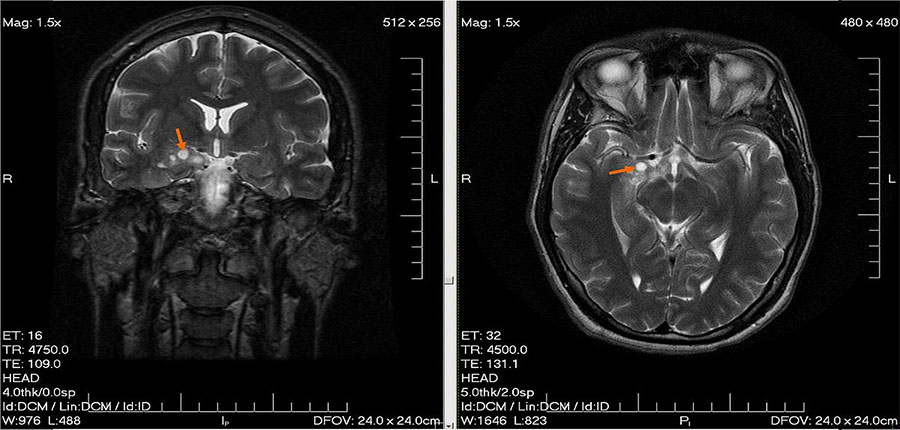

L’examen fut mené rapidement, et à la surprise du radiologue, ce n’était pas une simple anomalie de l’oreille interne qu’il découvrit, mais une tumeur maligne, cachée en profondeur dans le lobe temporal de son cerveau.

Un simple examen d’imagerie pour analyser son nerf optique révéla un glioblastome, une tumeur maligne dissimulée près de son chiasma optique.